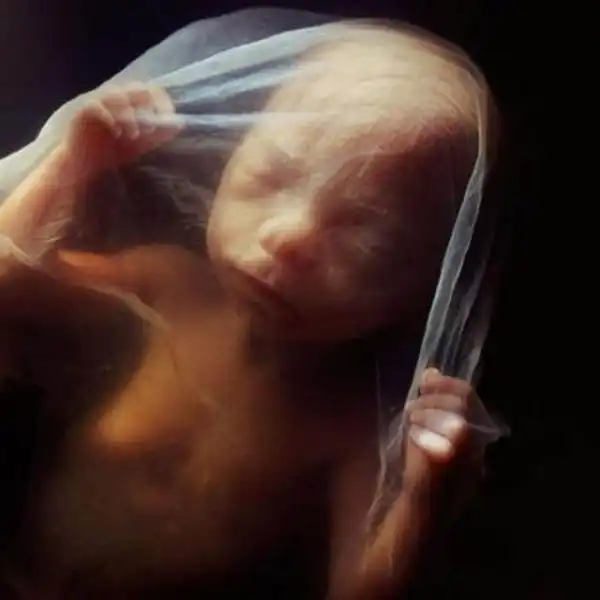

Восемь недель. Быстрорастущий эмбрион хорошо защищен во чреве матери. С помощью электронного микроскопа Нильссон смог увеличить изображение в сотни тысяч раз.